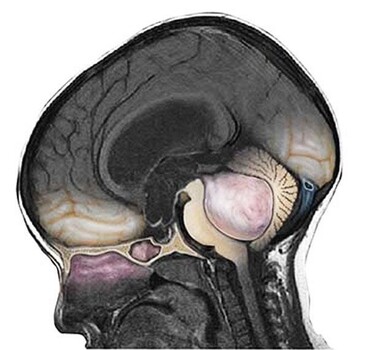

Медуллобластома мозжечка (medulloblastoma) – это злокачественное новообразование, поражающее клетки мозга человека. Чаще всего оно образуется в мозжечке, в его черве, из клеток, которые представляют собой незрелые элементы вспомогательной ткани – глии.

Медуллобластома мозжечка и головного мозга – это опухоль, которая формируется в задней черепной ямке. Это заболевание имеет и другие названия:

У взрослых классическая медуллобластома может локализоваться в области червя мозжечка. В детском возрасте опухоль может располагаться и в полушариях мозжечка.

Нейроглиома может классифицироваться по нескольким признакам. В зависимости от расположения новообразования можно выявить опухоль червя (в 80% случаев) и опухоль полушарий (в 20% случаев).